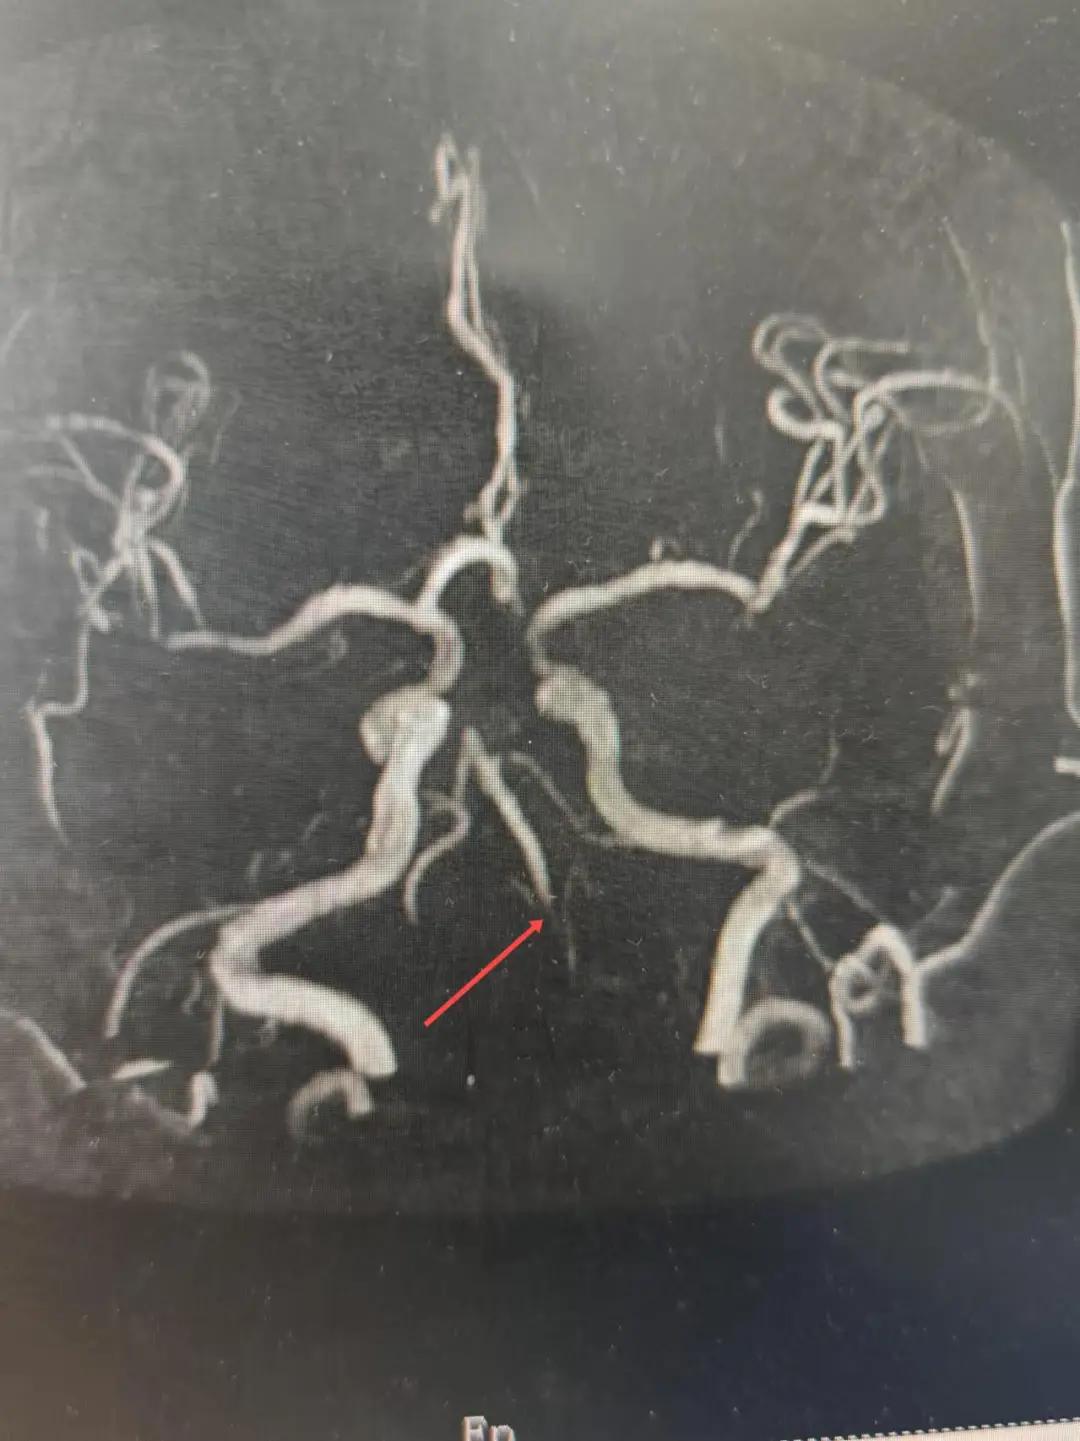

2024年12月19日,漯河市中醫(yī)院腦一科收治了一位79歲的女性患者?;颊咴谌朐呵?小時出現(xiàn)言語不利,右側肢體無力。腦一科醫(yī)師關卓杰接診后,全面評估患者病情,給予其靜脈溶栓,并急查頭顱MR。影像可見腦干、雙側枕葉、左側海馬旁回及丘腦新發(fā)梗塞灶,基底動脈閉塞。患者在靜脈溶栓完畢后仍出現(xiàn)陣發(fā)性言語不利、右側肢體無力、頭暈。立即進行科室間會診,副主任醫(yī)師彭壯考慮患者出現(xiàn)上述癥狀與其基底動脈閉塞后顱內動脈代償不良有較大關系,且基底動脈閉塞有較高的致死率與致殘率,建議行急診取栓,降低患者死亡及殘障風險。家屬了解病情,知情同意后要求行介入治療。

磁共振MRA提示基底動脈閉塞